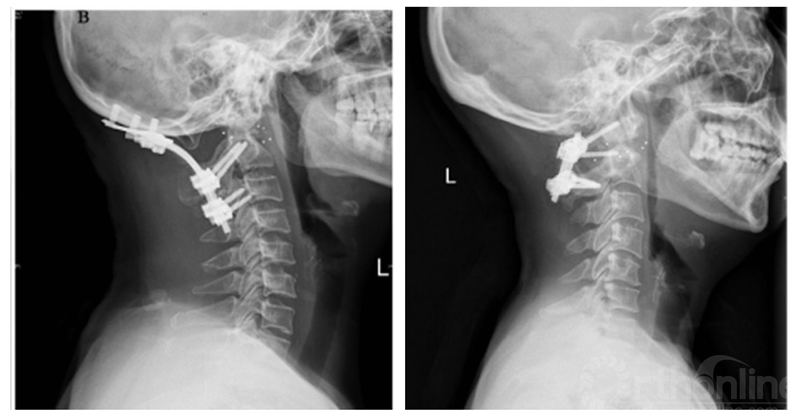

术后X线